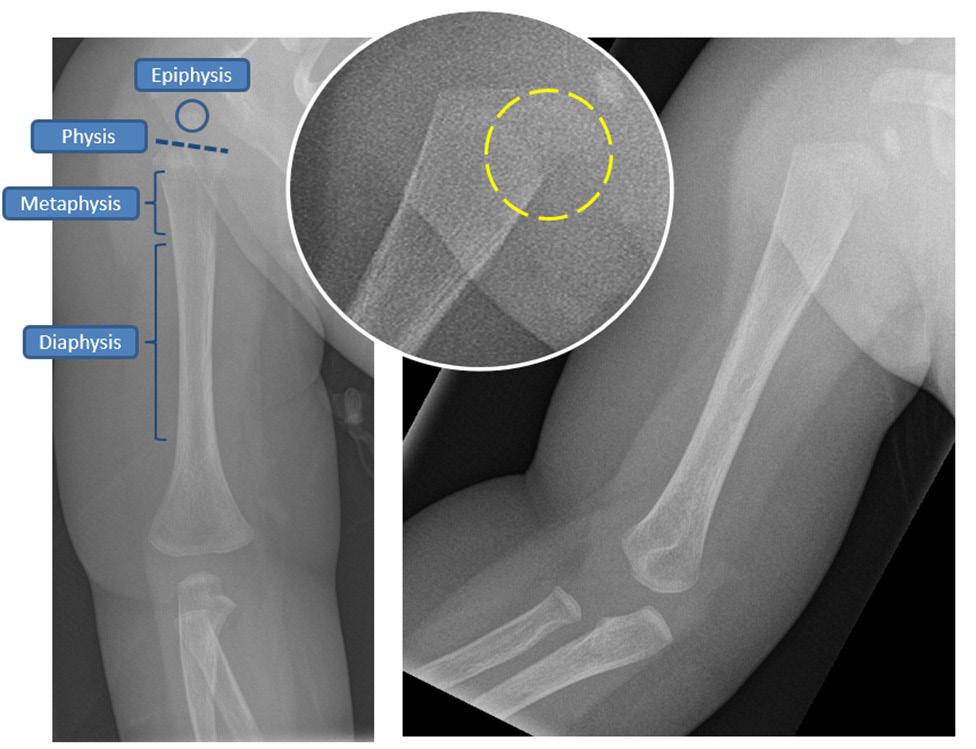

On examination, the infant is unsettled and has a temperature of 39C. There is no obvious erythema, warmth or deformity around the shoulder girdle. They seem irritable with movement of their right shoulder and abduction is limited to 90 degrees. They have a warm hand and a strong radial pulse. Their ear, nose, throat, abdominal and cardiovascular examination are unremarkable. Radiographs of their right humerus are shown in Figure 1. Bloods demonstrate a CRP of 26 and WCC of 7 × 109/L with a normal neutrophil count. Blood cultures are taken.

Radiographs (Figure 1) are reported as showing no fractures, but possible osteomyelitis due to the lucency seen in the proximal humerus which may represent a Brodie’s abscess or subperiosteal collection.